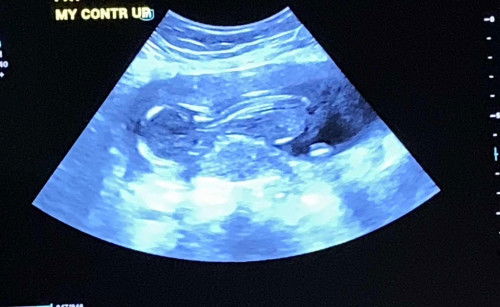

14 weeks pregnant

Ok lang po kaya si baby? SVP- 3.18cm normal lang po kaya sa 14 weeks? Ihi po kasi ako ng ihi. Inum din ako ng inum ng tubig. Noong check up- 151 HB ni baby Kinabukasan 125-130 HB na lang ni baby normal lang po ba? 2nd pregnancy ko na po ito. 1st pregnancy 33 weeks nawalan ng HB due to pre eclampsia

Sa 14 weeks na pagbubuntis, natural lang na mag-alala at maging mas mapanuri. Unahin natin ang SVP (Subchorionic Venous Pooling) na 3.18cm ay karaniwang itinuturing na normal, ngunit mahalaga pa rin na ipaalam ito sa iyong OB-GYN para makasigurado. Tungkol sa madalas na pag-ihi, ito ay normal din sa pagbubuntis dahil sa hormonal changes at ang paglaki ng uterus na bumibigat sa iyong bladder. Ang pag-inom ng maraming tubig ay mabuti para maiwasan ang dehydration, kaya't ituloy mo lang ito. Ang pagbabago sa heart rate (HB) ng baby mula 151 pababa sa 125-130 ay maaaring normal. Sa loob ng sinapupunan, ang heart rate ng baby ay maaaring magbago depende sa iba't ibang factors tulad ng aktibidad ng baby at iyong hydration levels. Ngunit dahil nagkaroon ka ng pre-eclampsia sa unang pagbubuntis, mas mabuting magpakonsulta agad sa iyong doktor para matiyak na nasa maayos na kalagayan si baby at ikaw. Para naman sa dagdag na suporta sa iyong kalusugan at produksyon ng gatas, maari kang uminom ng mga suplemento para sa buntis at nagpapasusong ina. Makakatulong ito upang mapanatili kang malusog at masigla habang nagbubuntis. Maari mong tignan ang link na ito para sa mga suplemento: [link](https://invl.io/cll7hs3). Laging tandaan na ang pinakamahalaga ay ang regular na konsultasyon sa iyong OB-GYN upang masigurado ang kaligtasan mo at ni baby. Huwag mag-atubiling magtanong at humingi ng payo sa kanila. Ingat lagi at sana'y maging maayos ang iyong pagbubuntis! https://invl.io/cll7hw5

Magbasa paalam ko ang minimum to consider sa normal SVP ay 5 cm. anong sinabi ng ob nyo po tungkol dito? baka mahirapan po si baby gumalaw dahil low amniotic fluid, increase water intake. kain fruits at masasabaw na pagkain. contact your OB asap to clarify para di ka magworry. mas mabuting sya po unang iask nyo kasi sya naman po nakakamonitor ng pregnancy nyo